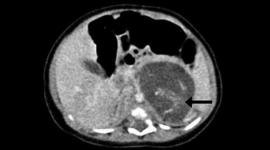

طفلة تولد بهونغ كونغ وهي تحمل جنينين بأحشائها